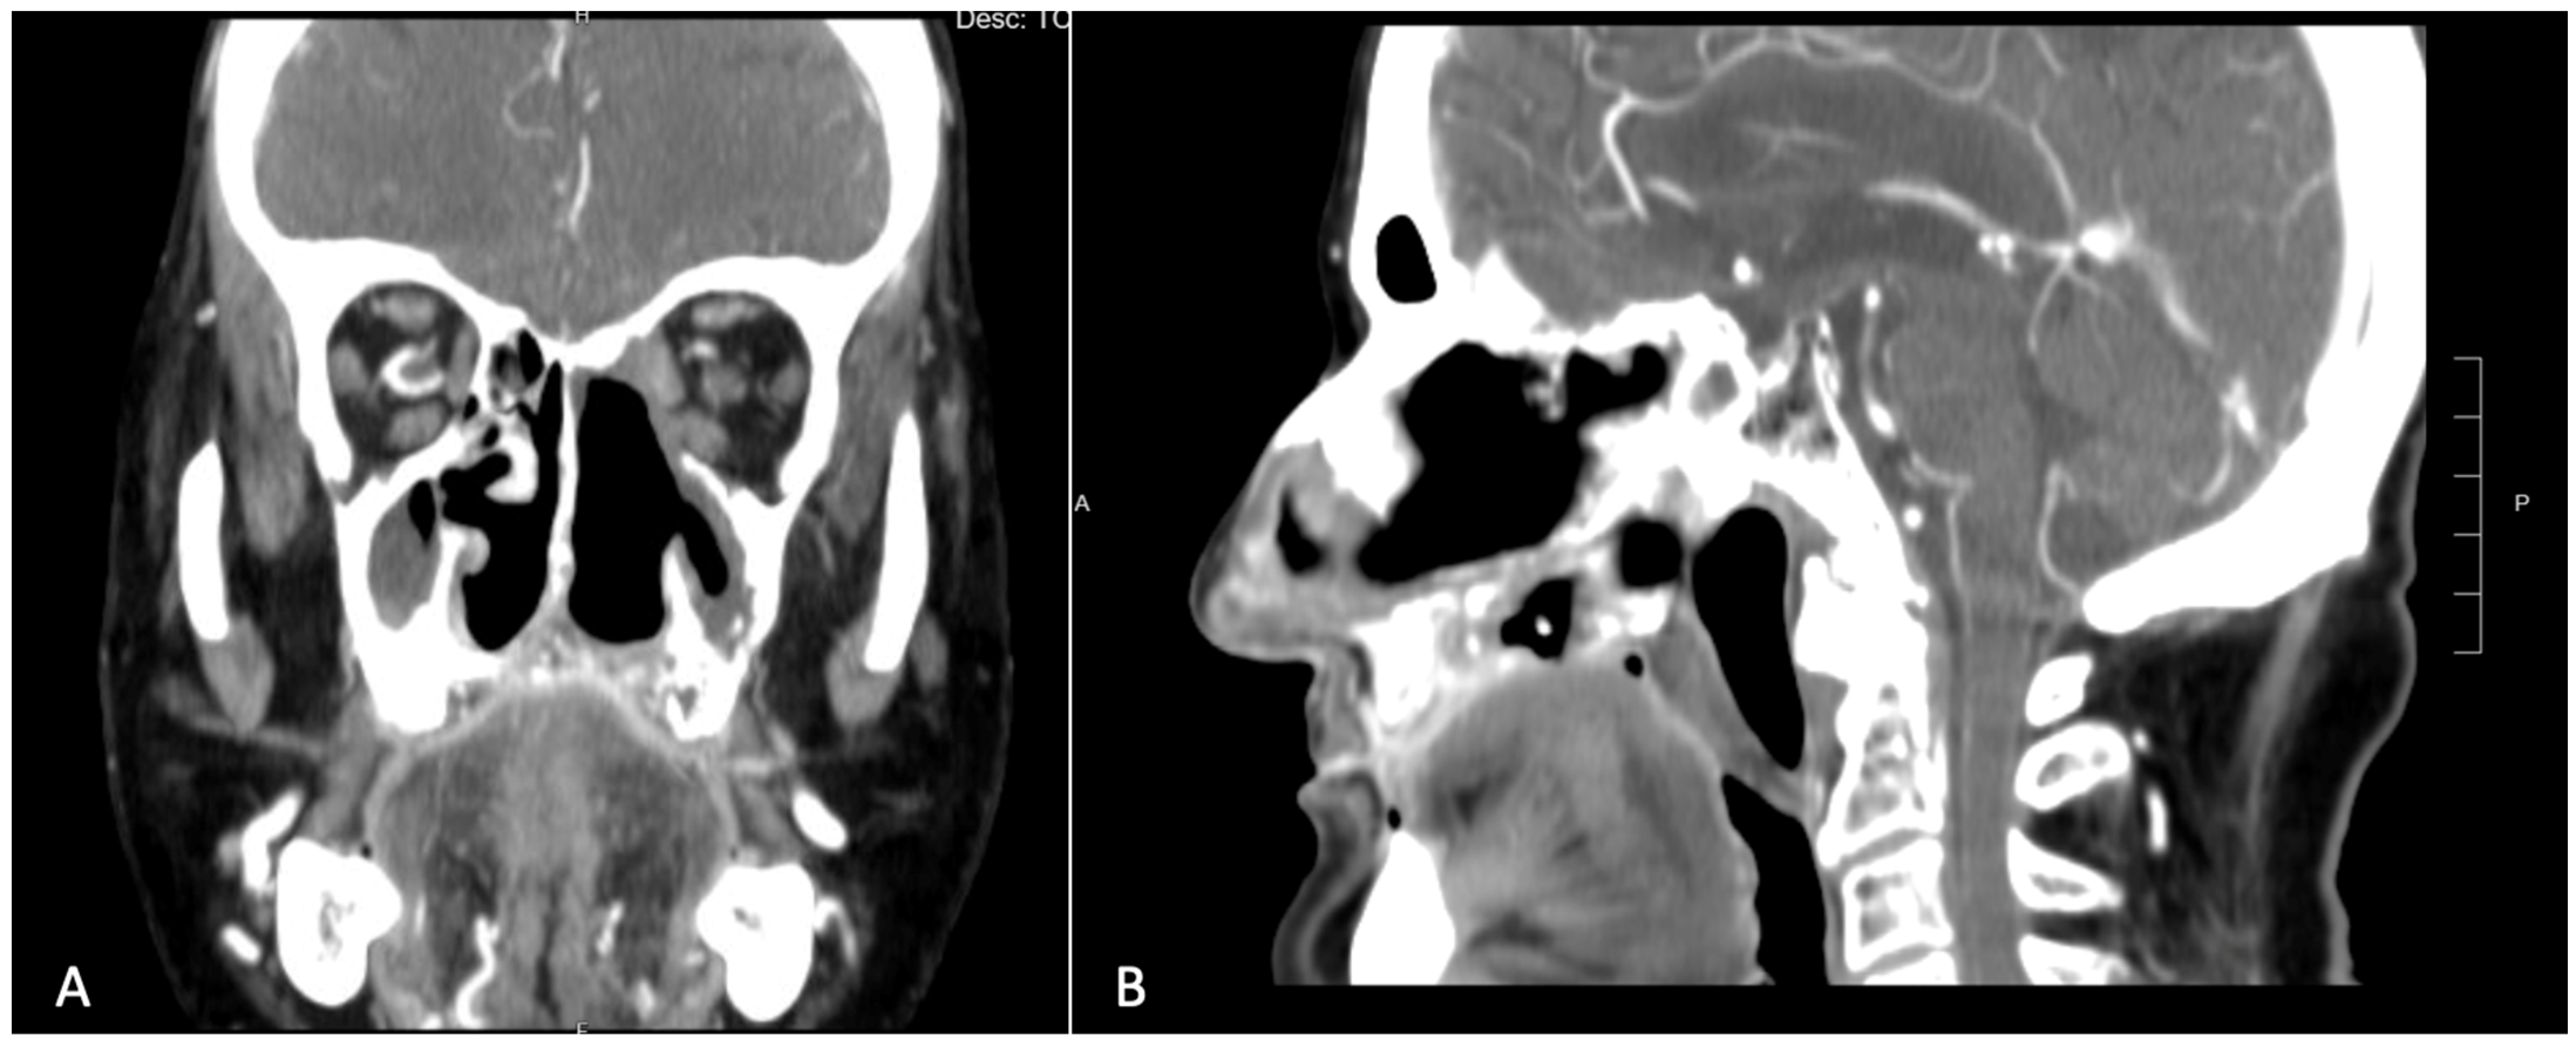

An incisional biopsy of the lesion confirmed the diagnosis of squamous cell carcinoma. The patient then underwent a contrast-enhanced CT scan, which revealed a large area of osteolysis involving the left maxilla, extending beyond the midline and encompassing the entire pre-maxilla [Figure 2]. Neck scans showed no suspicious lymphadenopathy.

Figure 2.

Pre-operative CT scan showing a large area of osteolysis involving the left maxilla which exceeded the midline and the entire premaxilla. (A) Coronal view. (B) Sagittal view.